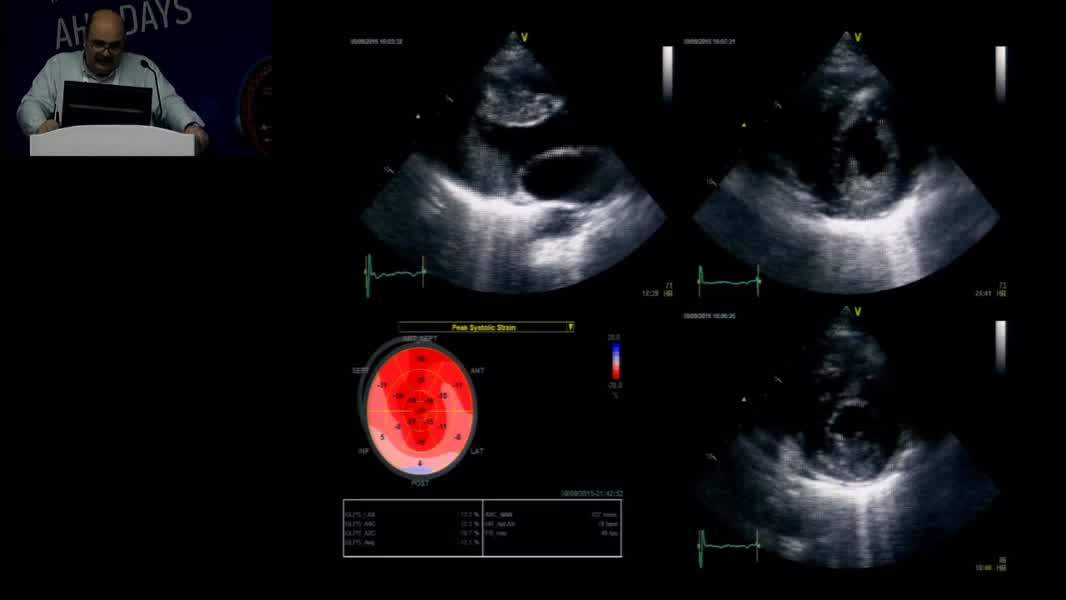

Echocardiographic Face Of Rare Cardiomyopathy And Fabry: Hands On Practical Echocardiography Course In The Diagnosis Of Fabry Disease And Cardiomyopathy Omaç Tüfekçioğlu (TR)

Nadir Miyokardiyopati ve Fabry’nin Ekokardiyografik Yüzü